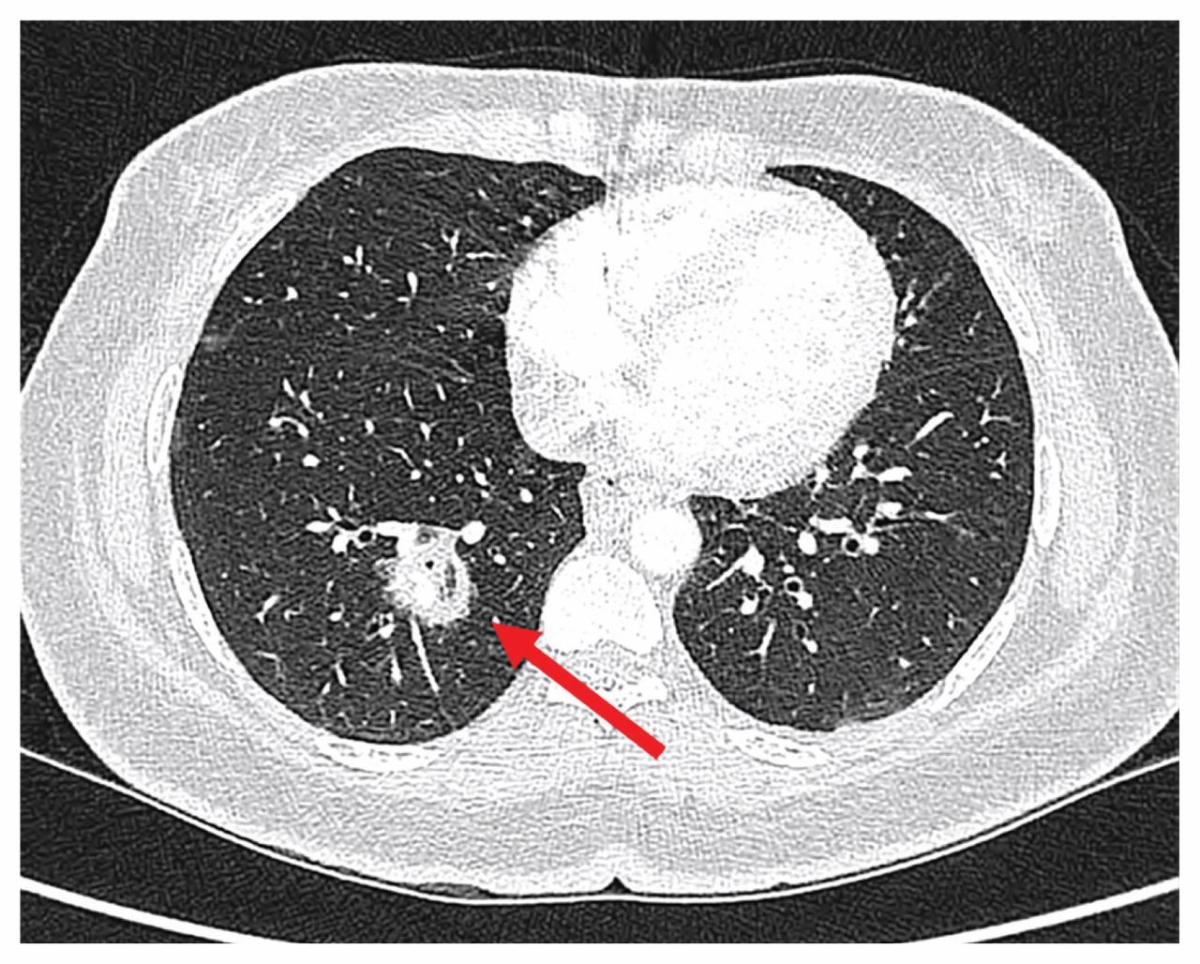

Bác sĩ Nguyễn Kim Anh, Bệnh viện Bệnh Nhiệt đới Trung ương cho biết từ những dấu hiệu "không khớp" này, ê-kíp đã chủ động mở rộng chẩn đoán, chỉ định chụp CT xoang để loại trừ các bệnh lý vùng mũi xoang. Kết quả hình ảnh cho thấy tổn thương xoang hàm có đặc điểm gợi ý nhiễm nấm xâm lấn kèm theo dấu hiệu ăn mòn cấu trúc xương xoang.

Dựa trên lâm sàng và hình ảnh học, bệnh nhân được chẩn đoán nhiễm nấm đen xâm lấn xoang hàm (Mucormycosis) - một bệnh lý hiếm gặp nhưng cực kỳ nguy hiểm, có khả năng tiến triển rất nhanh và đe dọa trực tiếp đến tính mạng. Ca bệnh lập tức được hội chẩn liên chuyên khoa và chỉ định phẫu thuật cấp cứu tối khẩn nhằm ngăn nấm lan vào ổ mắt và não.